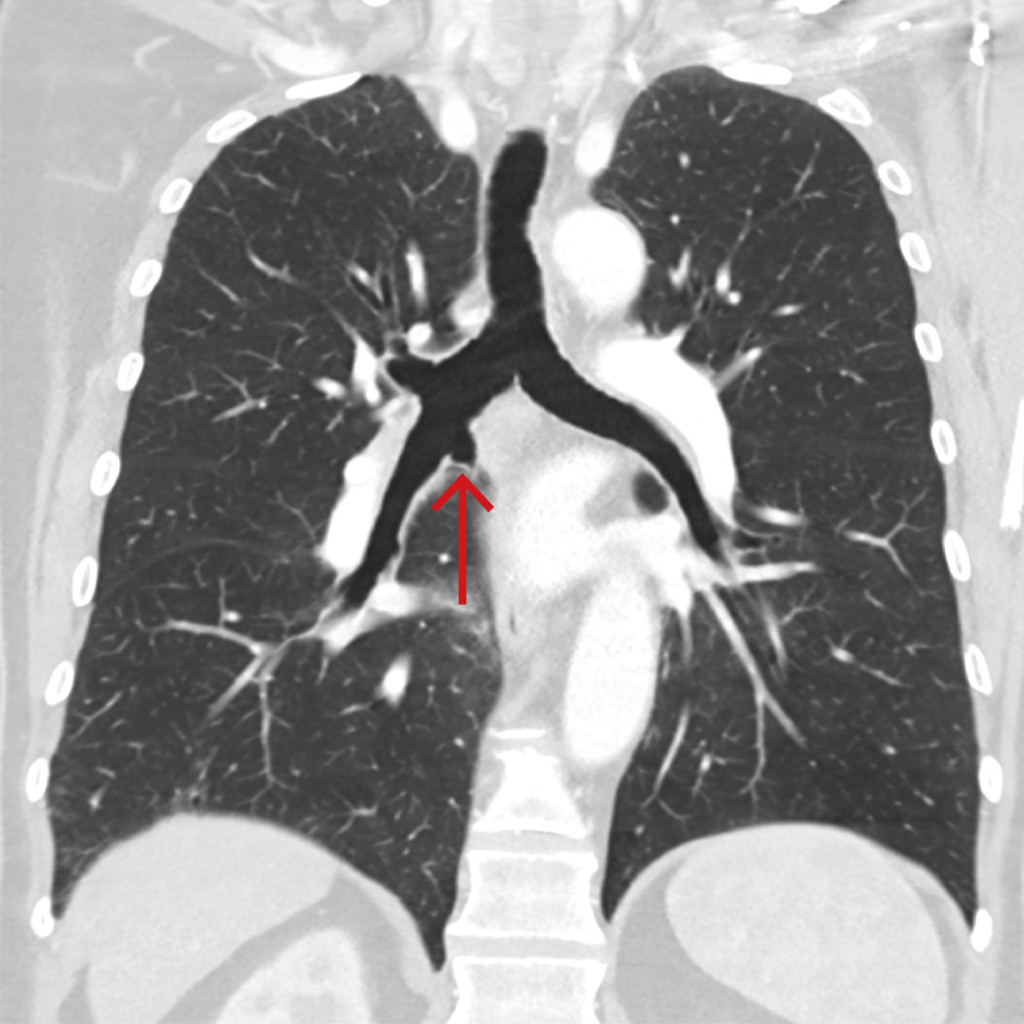

CT-bildet viser en medfødt aksessorisk kardial bronkus som går av fra bronchus intermedius. Pasienten var en eldre mann uten symptomer fra luftveiene, og funnet var tilfeldig. Som ledd i videre utredning ble han bronkoskopert. Bronkoskopien viste, i samsvar med CT, en recess i proksimale bronchus intermedius, pekende i kardial retning. Slimhinnen var normal, og det ble ikke tatt prøver fra området.

Aksessoriske bronkier er sjeldne, anatomiske varianter med en anslått forekomst på 0,07–0,5 % (1). De oppstår hovedsakelig i høyre hovedbronkus eller bronchus intermedius og dannes i tidlig fase (4.–6. svangerskapsuke) av utviklingen av luftveiene. Aksessoriske bronkier har normal slimhinne og veggbrusk. I halvparten av tilfellene ender recessen blindt, men hos øvrige kan de forgrene seg og forsyne tilhørende underutviklede lobuli. De fleste aksessoriske bronkier er asymptomatiske og oppdages tilfeldig på CT toraks. Der recessen kommuniserer med lungevev, kan dette disponere for luftveisinfeksjoner. Hemoptyse og malign transformasjon er beskrevet, og kirurgisk fjerning er da aktuelt (2, 3). Kardiale bronkier kan forveksles med distale trakeale divertikler («grisebronkus»). Asymptomatiske aksessoriske bronkier trenger ikke å kontrolleres.